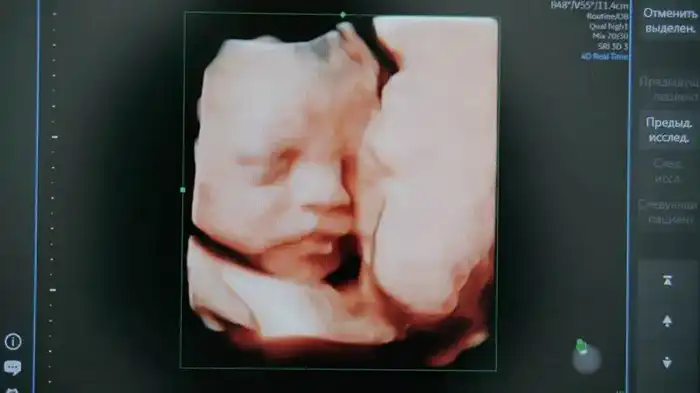

В Карагандинской области стартует новый пилотный проект, который направлен на раннее выявление spina bifida — редкой патологии развития плода. Инициаторами выступили Yandex Qazaqstan и региональное управление здравоохранения, при поддержке акимата области. Проект будет реализован с использованием искусственного интеллекта для анализа УЗИ-снимков.

Система предназначена для работы с изображениями, полученными на первом скрининге, который проводится на 11—14 неделе беременности. Заместитель акима региона Ораз Таурбеков отметил, что выбор Карагандинской области в качестве пилотного региона обусловлен высоким уровнем цифровизации. "Мы уверенно развиваемся в этой сфере, что подтверждают предыдущие проекты, такие как Damumed и ОСМС," — добавил он.

Искусственный интеллект будет анализировать результаты УЗИ беременных, обрабатывая только изображения без использования персональных данных. Для хранения и обработки данных будут применяться облачные технологии Yandex Cloud. Анна Лемякина, руководитель Центра технологий для общества при Yandex Qazaqstan, отметила, что нейросеть станет важным помощником для врачей в процессе принятия решений.

Spina bifida — это врождённое заболевание, которое проявляется в неправильном формировании позвоночника и спинного мозга плода. Оно встречается примерно в одном случае на тысячу новорождённых и может привести к серьезным последствиям, включая паралич. Ранняя диагностика позволяет повысить шансы на успешное лечение, включая возможность проведения операции до 26-й недели беременности.